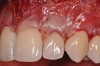

Various procedures to correct deficient gingival contours have been well documented in the dental literature.1,2 Increasing zones of attached gingiva using palatal donor tissue and the free gingival grafting procedure was introduced by Björn almost a half century ago.3 Using palatal donor tissue in the form of a free soft-tissue autograft for root-coverage procedures was reported by Miller.4 Additional procedures were reported using lateral5 or coronal repositioning6-8 of the adjacent attached gingiva via a pedicle flap or the coronal repositioning of previously grafted tissue.9,10 Miller also reported on gingival grafts placed over root surfaces to correct areas of deep-wide gingival recession.11 Further surgical advancements led to the use of subepithelial connective tissue from the palate to obtain root coverage.12-14 Figure 1 shows the pretreatment view of a mandibular central incisor, and Figure 2 depicts the post-treatment view of the site treated with a subepithelial connective tissue graft harvested from the patient’s palatal tissues.

Fig 1. Preoperative clinical view, mandibular central incisor.

Figure 1

Fig 2. Post-treatment clinical view after subepithelial connective tissue graft.

Figure 2